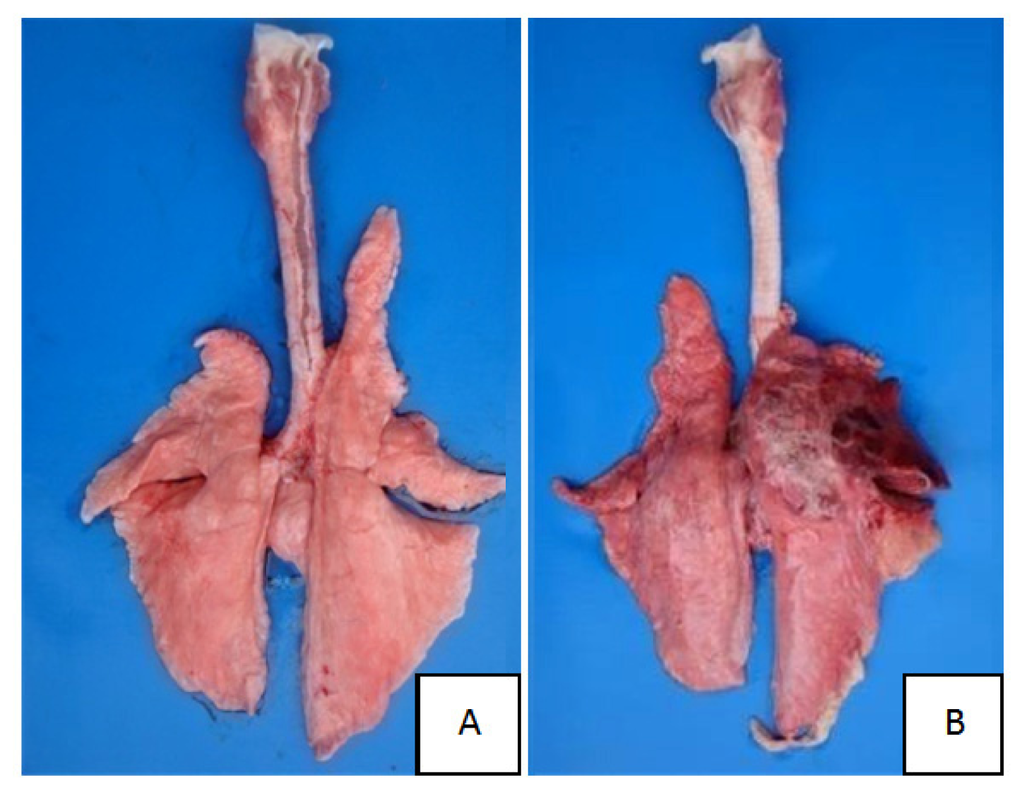

2.1. Clinical Symptoms and Necropsy Findings